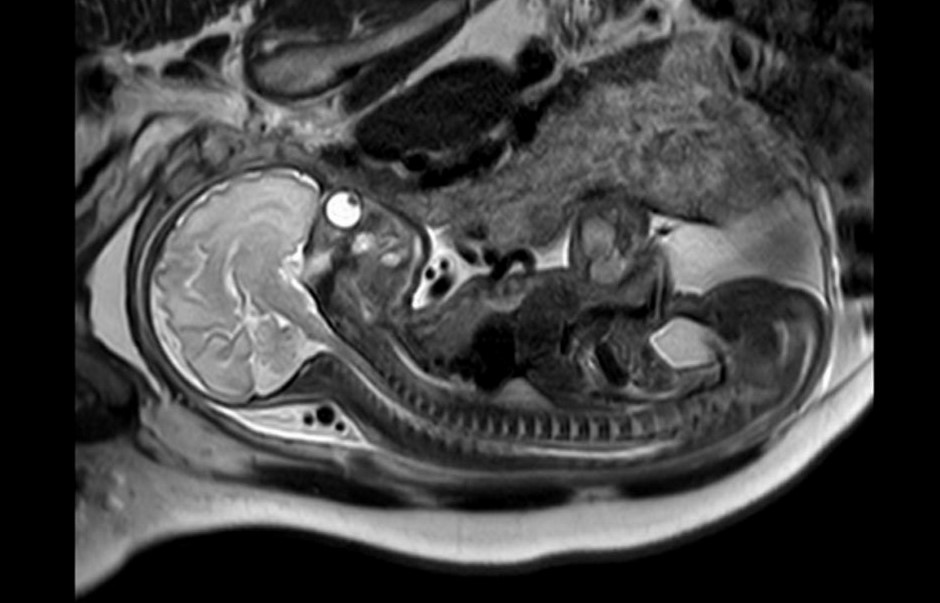

胎儿磁共振检查不存在电离辐射,它的视野大、软组织分辨率高,可以通过任意的切面扫描来显示胎儿的全貌。并且不受母体过度肥胖、羊水过少、多胎、母体子宫肌瘤、胎儿骨骼遮挡、孕晚期胎头入盆等情况的限制,尤其对胎儿颅脑发育评估有无可替代的优势。

1.诊断价值最大的是胎儿中枢神经系统异常:临床常见检查原因如后颅窝池宽,需要MRI来确认是否为Dandy-Walker畸形、Joubert综合征、蛛网膜囊肿、Blake囊肿等;后颅窝显示不清,需要除外ChiariⅡ畸形。其次为侧脑室宽,需要MRI确认是否合并胼胝体发育不全、结节性硬化、脑回发育畸形、脑出血、脑肿瘤、脑积水、积水性无脑、前脑无裂畸形、脑脊膜膨出等。确认超声软指标异常是否合并严重畸形对于妊娠结局至关重要。

8. 胎儿脊柱异常:如脊柱裂、脊髓脊膜膨出、脊髓栓系、半椎体、椎体冠状裂,骶尾部畸胎瘤等,胎儿MRI可以一目了然。